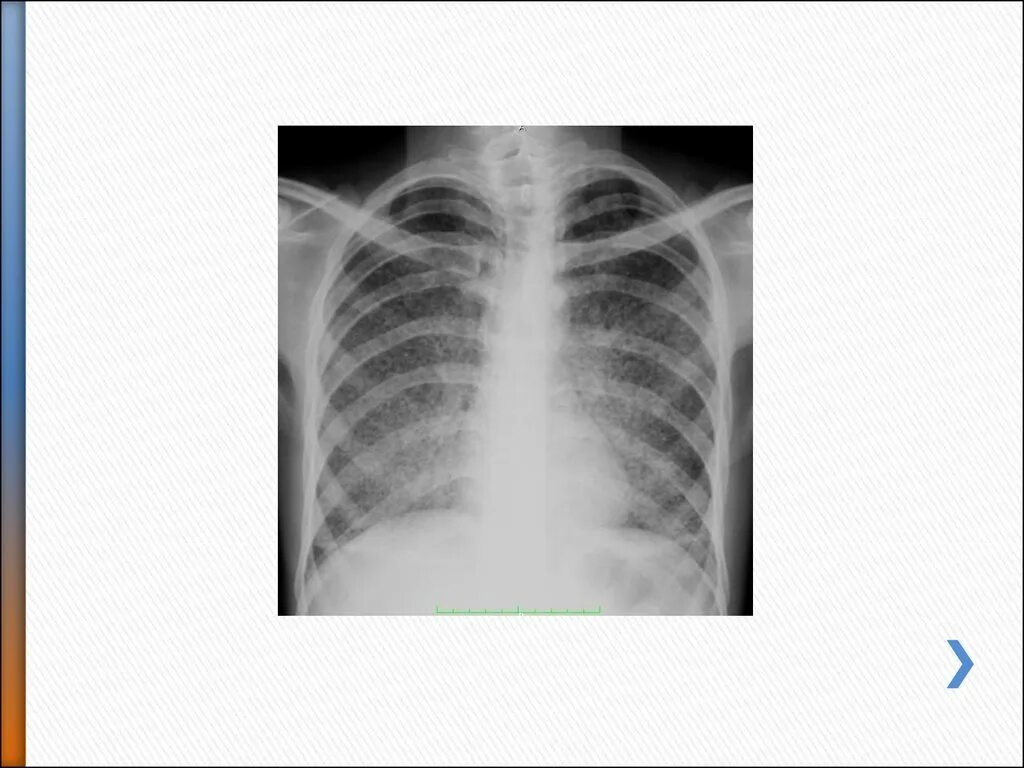

Диссеминированный туберкулез фаза инфильтрации